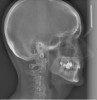

(4.) Lateral x-ray showing a retrognathic and entrapped mandible.

Figure 4